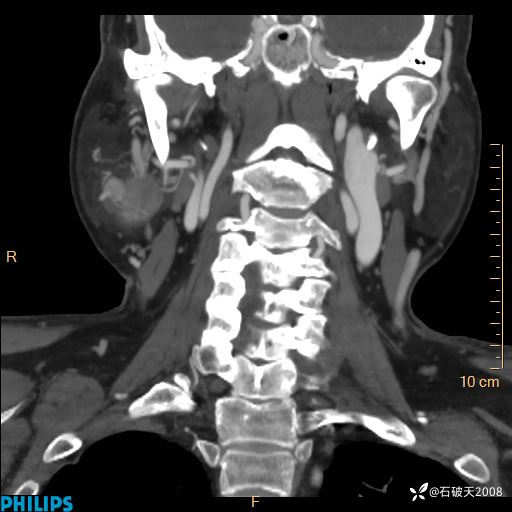

MIP